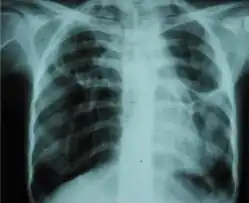

A fibrothorax can typically be diagnosed by taking an appropriate medical history in combination with the use of appropriate imaging techniques such as a plain chest X-ray or CT scan.[1] These imaging techniques can detect fibrothorax and pleural thickening that surround the lungs.[11] The presence of a thickened peel with or without calcification are common features of fibrothorax when imaged.[1] CT scans can more readily differentiate whether pleural thickening is due to extra fat deposition or true pleural thickening than X-rays.[1]

If a fibrothorax is severe, the thickening may restrict the lung on the affected side causing a loss of lung volume.[11] Additionally, the mediastinum may be physically shifted toward the affected side.[1] A reduction in the size of one side of the chest (hemithorax) on an X-ray or CT scan of the chest suggests chronic scarring.[9] Signs of the underlying disease causing the fibrothorax are also occasionally seen on the X-ray.[9] A CT scan may show features similar to those seen on a plain X-ray.[11] Lung function testing typically demonstrates findings consistent with restrictive lung disease.[9]

Chest X-ray showing bilateral fibrosis and pleural thickening in infection with non-tuberculosis mycobacteria.